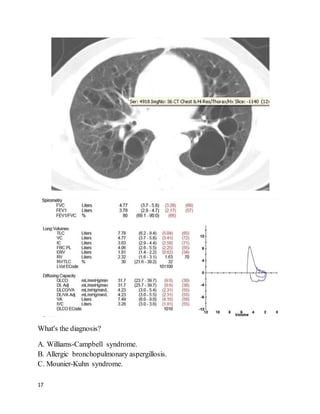

What's the diagnosis?

A. Williams-Campbell syndrome.

B. Allergic bronchopulmonary aspergillosis.

C. Mounier-Kuhn syndrome.

18

D. Cystic fibrosis.

E. Marfan syndrome.

We feelthat C is the best answer.

Mounier-Kuhn syndrome, or congenital tracheobronchomegaly, is a rare inherited

disorder of cartilage formation resulting in enlargement of the C-rings in the

segmental bronchi and trachea. More distal bronchial structures are normal. (This

is in contradistinction to Williams-Campbell syndrome, in which central airways

are normal but distal airways are dilated.) The diagnosis is readily made on a CT

scan showing grossly enlarged central airways, especially with compatible

symptoms.